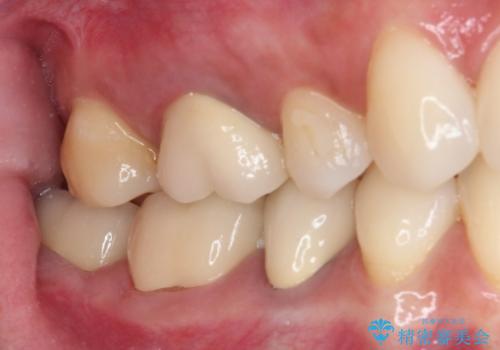

ドイツやベルギーなどで治療を受けた奥歯2本が食事の度にしみているとのことで、レントゲン検査や視診を行ったところ、補綴物や修復物の適合が悪く、それが原因であると考えられました。

いずれの歯も症状に異常なく、オールセラミッククラウンにて補綴治療を行うこととしました。

歯とクラウンの適合が良くなることで、食事の度にしみるという症状はなくなり、歯間部にものが挟まって不快な思いをすることもなくなりました。